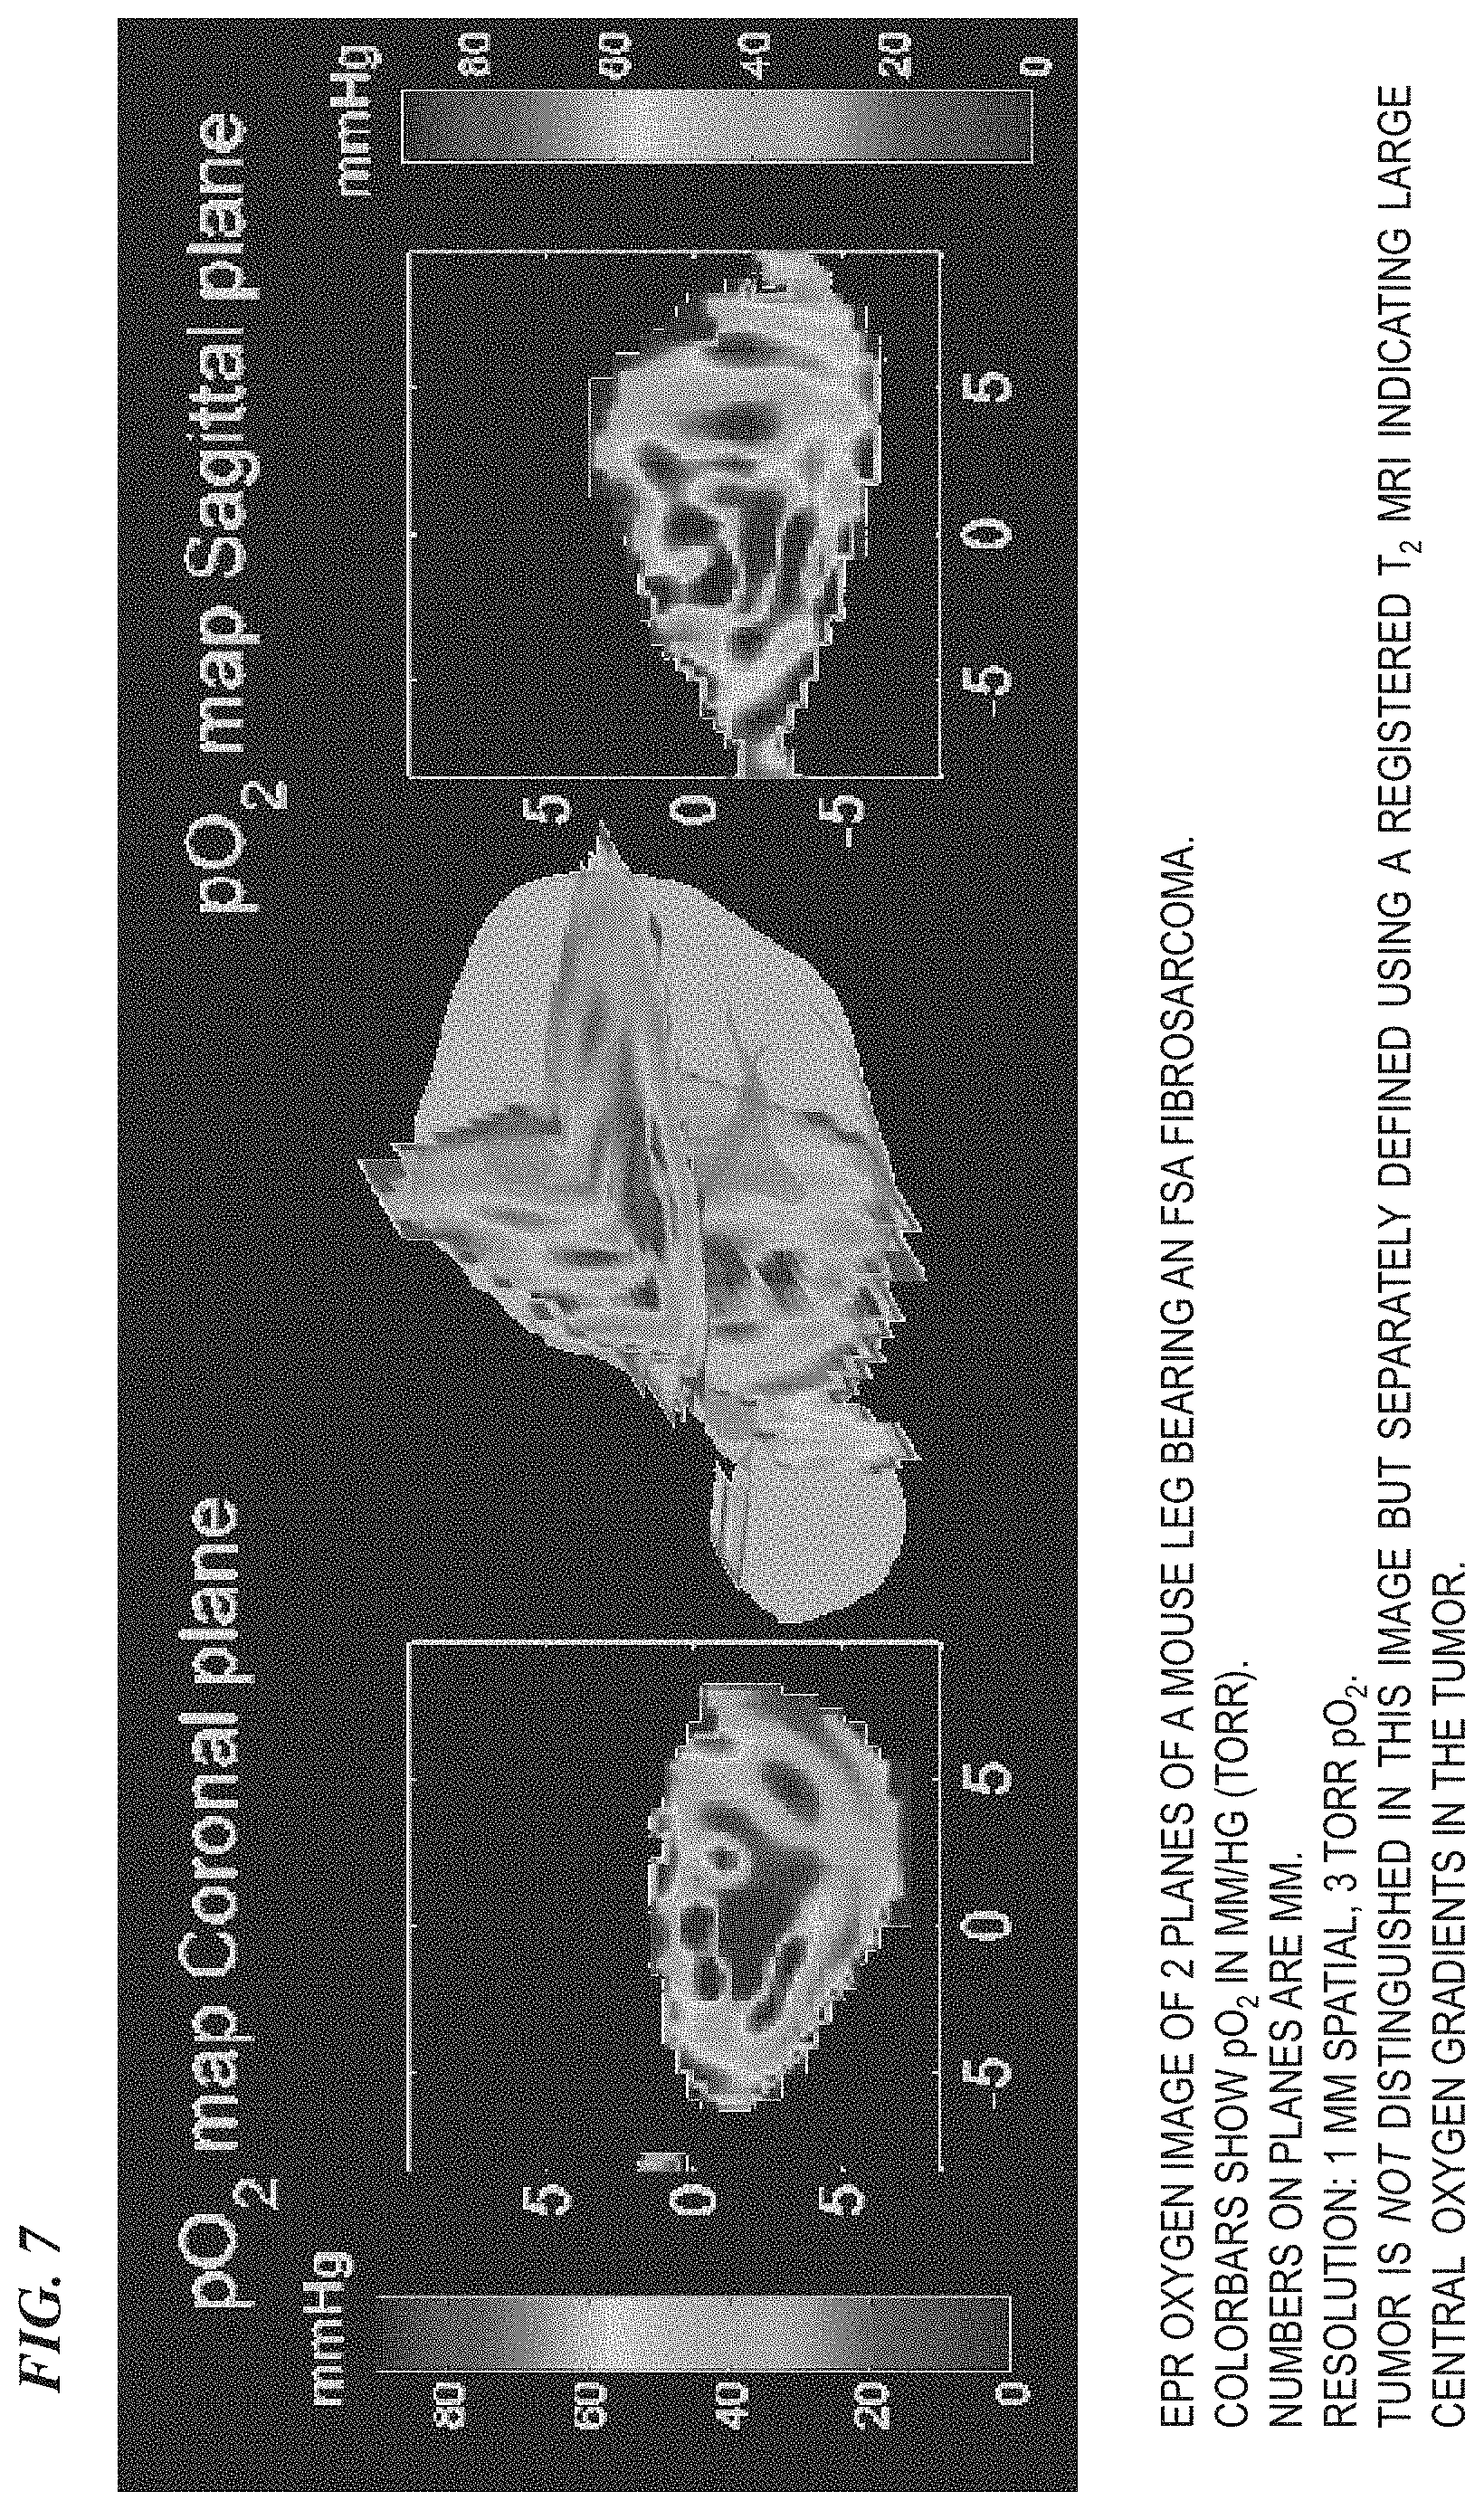

FIG. 7 is an EPR oxygen image of two planes of a mouse leg bearing an FSa fibrosarcoma.

FIG. 8 is an EPR oxygen image of two planes of a mouse leg bearing an FSa fibrosarcoma. Colorbars show pO2in mm/hg (torr). Numbers on planes are mm. Resolution: 1 mm spatial, 3 torr pO2. Tumor is not distinguished in this image but separately defined using a registered T2MRI indicating large central oxygen gradients in the tumor.